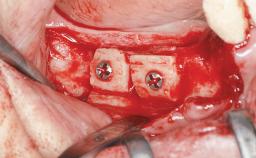

Replacement of Multiple Teeth in a Partially Dentate Posterior Mandible with a Fixed Dental Prosthesis Using a Flapless Approach

Guided Surgery Yes